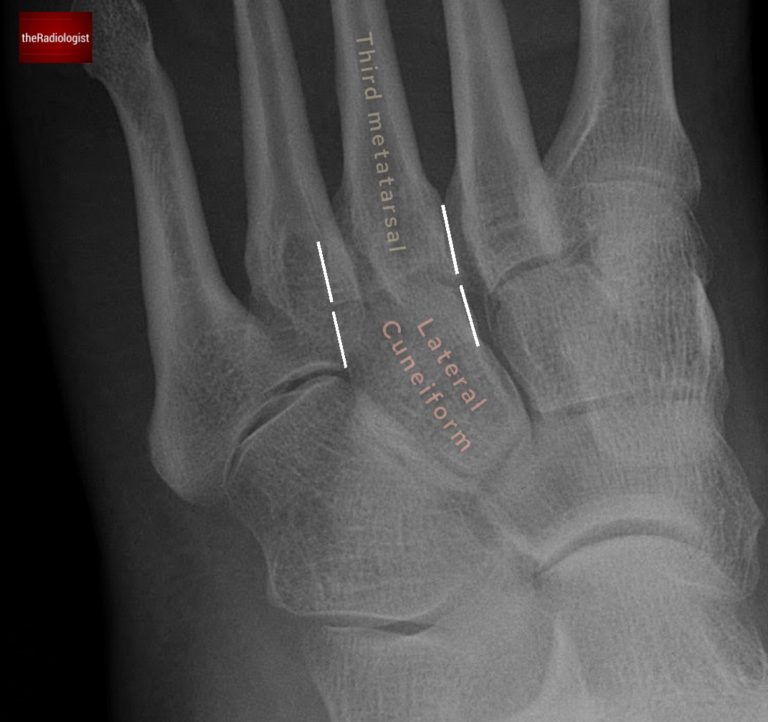

• Oblique view: the borders of the third metatarsal should line up with the lateral cuneiform.

Looking for Lisfranc injury (oblique view): on an oblique view look to see if the third metatarsal lines up with the lateral cuneiform.

Looking for Lisfranc injury (oblique view): in this case there is a subtle step between the lateral cuneiform and the third metatarsal. This is a Lisfranc injury.